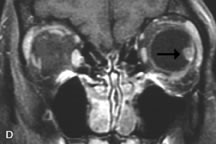

Lymphomas have MRI characteristics similar to those of inflammatory lesions in that they are hypointense to fat and isointense to muscle on T1-weighted images (Fig. 22). They may appear hyperintense to fat on T2-weighted images, perhaps owing to less fibrosis than that seen in orbital inflammatory pseudotumor, although this is not a consistent finding.31,50,66 Lymphoid tumors typically enhance moderately after contrast injection. Unfortunately, studies have shown that tumor density and homogeneity are similar between inflammatory and malignant orbital infiltrates, and MRI cannot differentiate these lesions.72,73

Fig. 22. A and B. T1- and (C) T2-weighted MR scans demonstrate a poorly defined multicompartmental mass enveloping the lateral rectus, superior rectus, and levator palpebrac superioris muscles. The lesion is isointense to brain on T1- and T2-weighted scans, as is typical for highly cellular neoplasms. D. Postcontrast fat-suppressed T1-weighted scan demonstrates intense enhancement of the infiltrating intraconal and extraconal tumor.